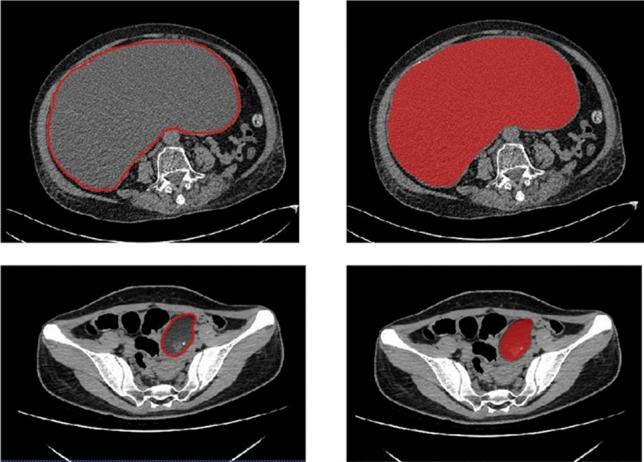

This paper develops a two-dimensional (2D) radiomics approach with computed tomography (CT) to differentiate between benign and malignant ovarian neoplasms. A retrospective study was conducted from July 2017 to June 2019 for 134 patients with surgically-verified benign or malignant ovarian tumors. The patients were randomly divided in a ratio of 7:3 into two sets, namely a training set (of n = 95) and a test set (of n = 39). The ITK-SNAP software was used to delineate the regions of interest (ROI) associated with lesions of the largest diameters in plain CT image slices. Texture features were extracted by the Analysis Kit (AK) software. The training set was used to select the best features according to the maximum-relevance minimum-redundancy (mRMR) criterion, in addition to the algorithm of the least absolute shrinkage and selection operator (LASSO). Then, we employed a radiomics model for classification via multivariate logistic regression. Finally, we evaluated the overall performance of our method using the receiver operating characteristics (ROC), the DeLong test. and tested in an external validation test sample of patients of ovarian neoplasm. We created a radiomics prediction model from 14 selected features. The radiomic signature was found to be highly discriminative according to the area under the ROC curve (AUC) for both the training set (AUC = 0.88), and the test set (AUC = 0.87). The radiomics nomogram also demonstrated good calibration and differentiation for both the training (AUC = 0.95) and test (AUC = 0.96) samples. External validation tests gave a good performance in radiomic signature (AUC = 0.83) and radiomics nomogram (AUC = 0.95). The decision curve explicitly indicated the clinical usefulness of our nomogram method in the sense that it can influence major clinical events such as the ordering or abortion of other tests, treatments or invasive procedures. Our radiomics model based on plain CT images has a high diagnostic efficiency, which is helpful for the identification and prediction of benign and malignant ovarian neoplasms.